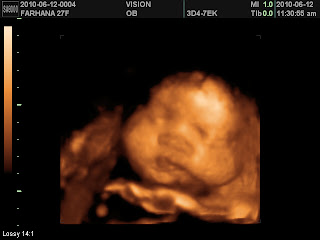

12 Jun ~ Buat 3D scan @ vision college..bb sangat comel..tengok dia move, smile, n ppnya sgt tembam!

ni la bb sy ms dlm perut, bila digeletek suh dia move, dia senyum2..kiut kan!

tengok pp dia..bb suka minum susu anmum!